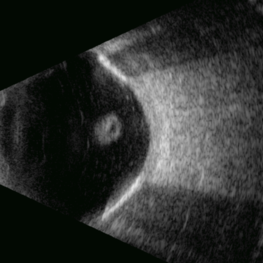

This B-mode longitudinal ultrasound scan demonstrates a long-standing rhegmatogenous retinal detachment, showing a characteristic open funnel configuration. The findings are consistent with chronic retinal detachment.

Photographer: Gustavo U. Fonseca Aguirre, Hospital Conde de Valenciana, Ciudad de México

Imaging device: Funnel

Condition/keywords: open funnel RD, Retina detachment